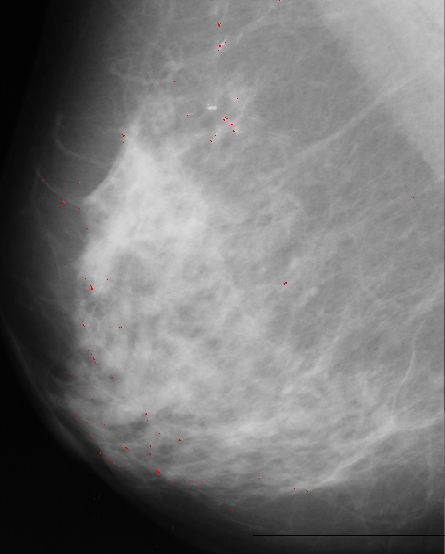

There are many black pixels, and few bright pixels. The selected threshold is at the first position in the histogram where the difference between two consecutive positions is smaller then a given value. After that we eliminate the shapes with areas bigger than given threshold. The result of this approach is presented bellow:

As we can see this approach is very noisy, contain many false-positives.